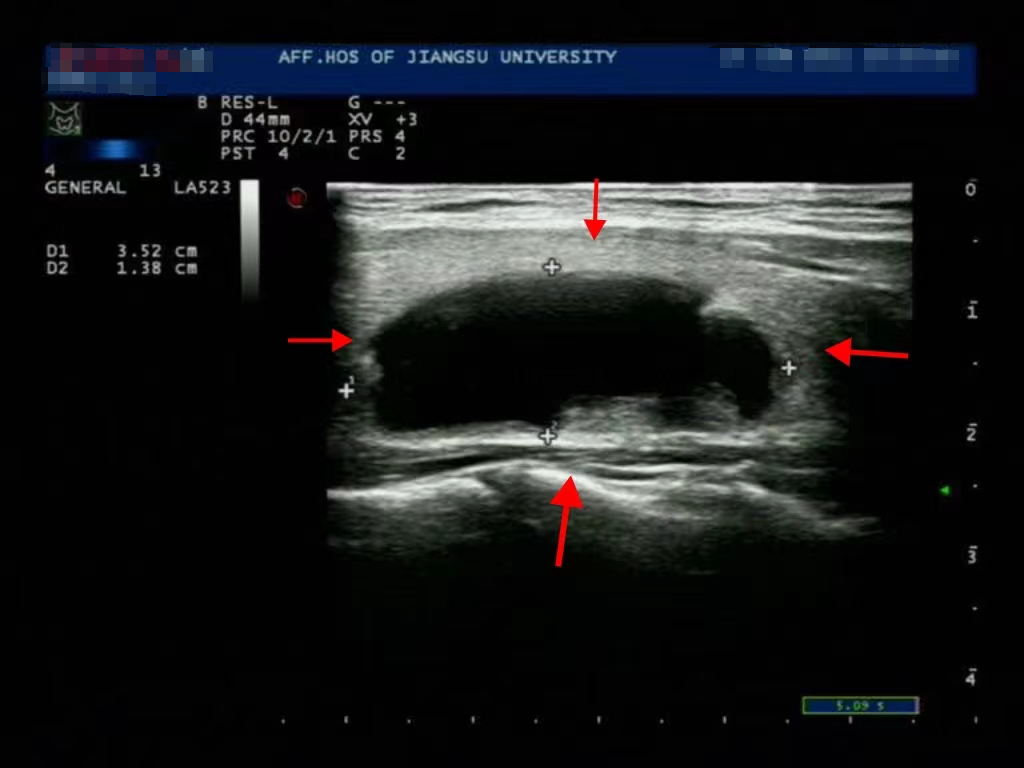

消融前

微波针是什么以“针”代“刀”,带你了解甲状腺结节微波消融术_https://www.jmylbn.com_新闻资讯_第11张

消融后3个月